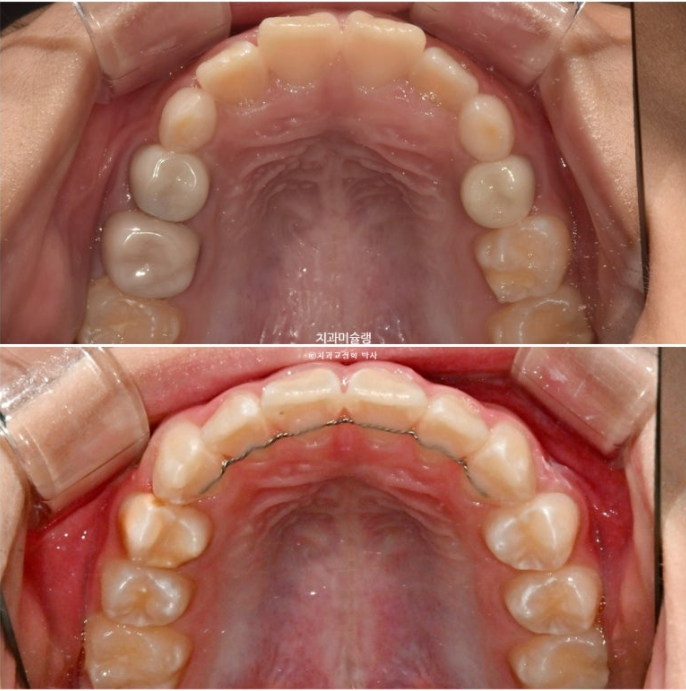

이제 전 후 비교 볼게요

23.10~25.11

나중에 성인이 되어 2차교정을 안해도 될 정도의 완성도 입니다.